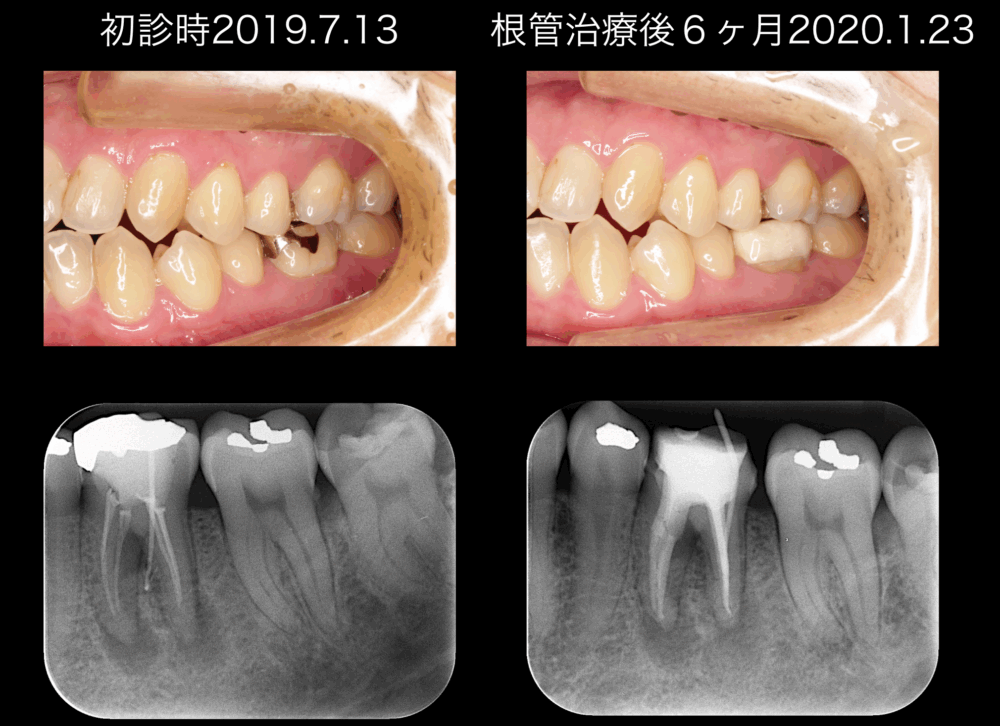

ももこ歯科のブログを読んでくださる皆様、いつもありがとうございます。 今回のブログは、前回のつづきで、深い歯周ポケットをともなうサイナストラクトがある歯内歯周病変のケースが、根管治療を行った結果どうなったかをお話しします...

ももこ歯科のブログを読んでくださる皆様、いつもありがとうございます。 今回のケースは、サイナストラクトがあり、深い歯周ポケットが存在する歯内歯周病変です。前回までのケース:サイナストラクトがあり、浅い歯周ポケットが存在す...